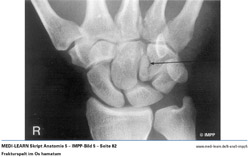

• Frakturspalt im Os hamatum